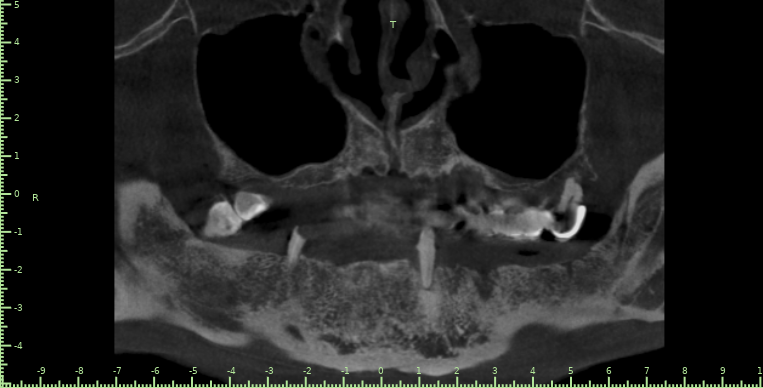

Geronima Опубликовано 29 апреля, 2022 Поделиться Опубликовано 29 апреля, 2022 Здравствуйте ! Был недавно в минской стоматологии где к сожалению мне не смогли помочь. В Финансах не ограничен. Нужны зубы, посоветуйте чтобы было качественно и надежно. Одномоментную имплантацию не рассматриваю вообще. К хорошему специалисту готов лечь в кресло хоть завтра. 3D Снимок зубов на гугл диске. https://drive.google.com/file/d/1Qx95HXPfq-zzHC1rwvTu9yMXEnugwHR-/view?usp=sharing Ссылка на комментарий